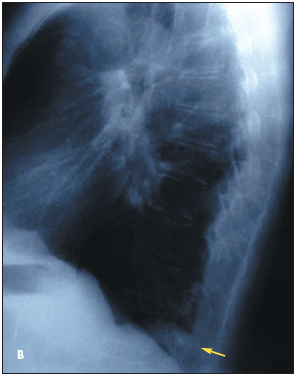

Routine chest radiographs reveal a left lower lobe density in a 70-year-old man (Figure 1 - Posteroanterior (A) and lateral (B) chest radiographs demonstrate a density in the left lower lobe). He has no chest pain, dyspnea, or hemoptysis.